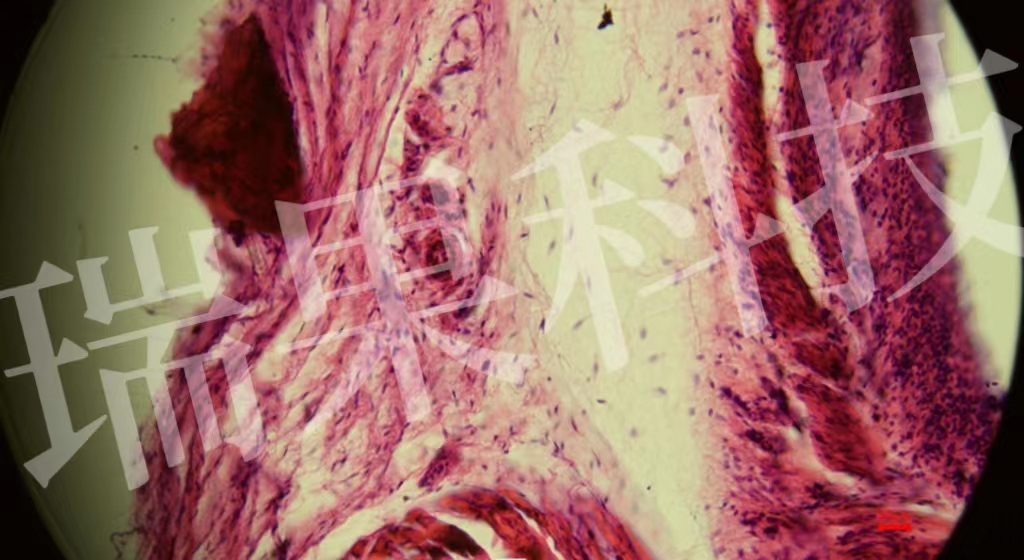

HE染色:苏木精 - 伊红染色法 ( hematoxylin-eosin staining ) ,简称HE染色法 ,石蜡切片技术里常用的染色法之一 。苏木精染液为碱性 ,主要使细胞核内的染色质与胞质内的核酸着紫蓝色 ;伊红为酸性染料 ,主要使细

HE染色:苏木精 - 伊红染色法 ( hematoxylin-eosin staining ) ,简称HE染色法 ,石蜡切片技术里常用的染色法之一 。苏木精染液为碱性 ,主要使细胞核内的染色质与胞质内的核酸着紫蓝色 ;伊红为酸性染料 ,主要使细胞质和细胞外基质中的成分着红色 。HE染色法是组织学、胚胎学、病理学教学与科研中最基本、使用最广泛的技术方法。

心1-1-20x

血清粘液腺-20x